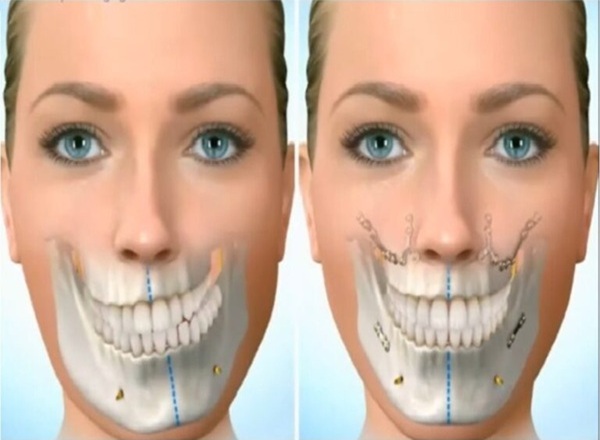

Cirugía Maxilofacial

La cirugía maxilofacial se encarga del diagnóstico y tratamiento quirúrgico de problemas que afectan dientes, encías, huesos maxilares y estructuras faciales. Realizamos procedimientos seguros y planificados para aliviar dolor, corregir alteraciones funcionales y mejorar la salud oral del paciente.

Desde extracciones complejas hasta cirugías reconstructivas, trabajamos con tecnología moderna y protocolos de bioseguridad que garantizan comodidad, precisión y una recuperación adecuada.

- ✓ Extracción de muelas del juicio y dientes retenidos

- ✓ Cirugía de infecciones y quistes odontogénicos

- ✓ Regularización ósea y preparación para implantes

- ✓ Duración: 45–120 minutos (según el procedimiento)